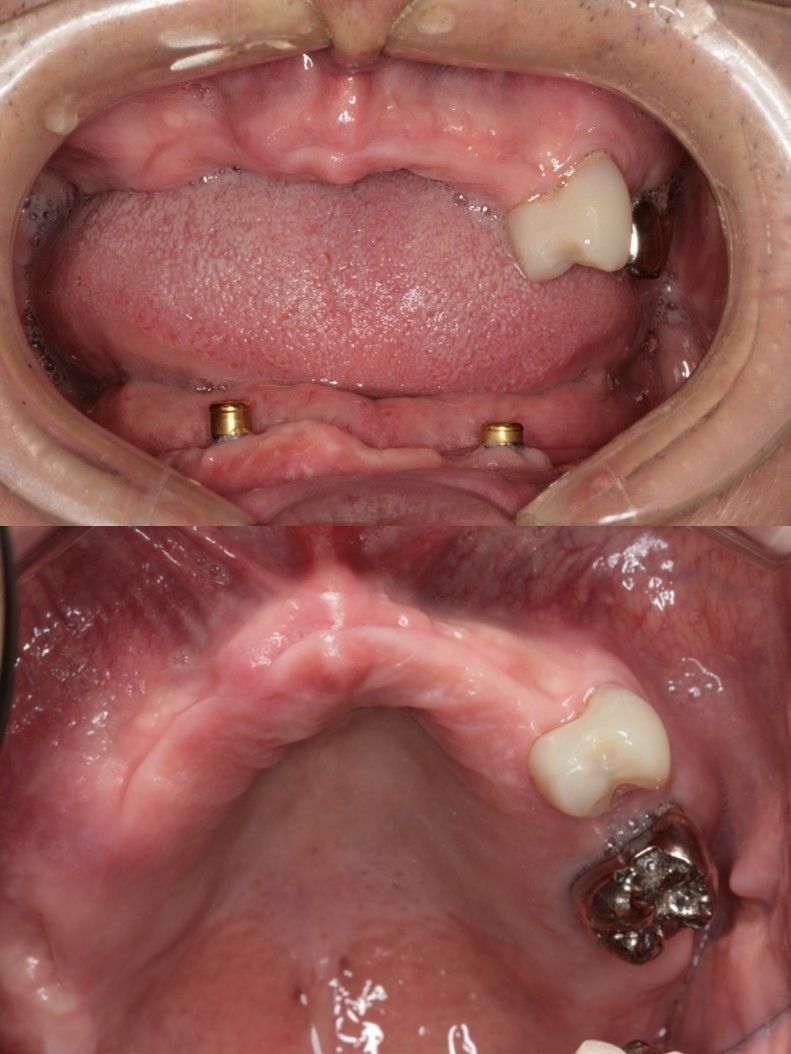

オールオン6(ボーンアンカードブリッジ)

インプラントオーバーデンチャー(ロケーターアタッチメントで義歯の維持)

| 年代 | 61歳 |

|---|---|

| 性別 | 男性 |

| 治療内容 | 上顎部分床義歯、下顎全部床義歯で咀嚼障害。高度の骨吸収(インプラント困難な症例) 上額のオールオン6インプラント治療。下顎インプラントオーバーデンチャーによる治療。 レントゲン診断、CT診断、補綴シミュレーション、血液検査、心電図、CT撮影ステント製作、サージカルガイド製作、治療用義歯、静脈内鎮静法抜歯、骨造成手術、サイナスリフト(上顎洞底挙上術)インプラント埋入、骨の治癒期間(4ヶ月)、静脈内鎮静法、2次手術、印象・咬合採得、インプラント上部構造装着、義歯装着、メインテナンス |

| 治療期間 | |

| リスク | 術中の不可抗力によるトラブル(出血など)、術後注意事項を守らないことによる疼痛、感染、上部構造装着後口腔内清掃を怠ったことによるインプラント周囲組織の炎症 |

| 副作用 | 治療後の口腔内清掃、及びメインテナンスを怠ったことによるインプラント周囲粘膜炎またはインプラント周囲炎 |

| 費用 | 4,400,000円(税込) (CT撮影診断、血液検査、心電図モニター、補綴シュミュレーション、治療用義歯、サージカルガイド製作、静脈内鎮静法、インプラント埋入、骨造成手術、サイナスリフト(上顎洞底挙上術)投薬、2次手術、印象・咬合採得、インプラント上部構造などを含む) |